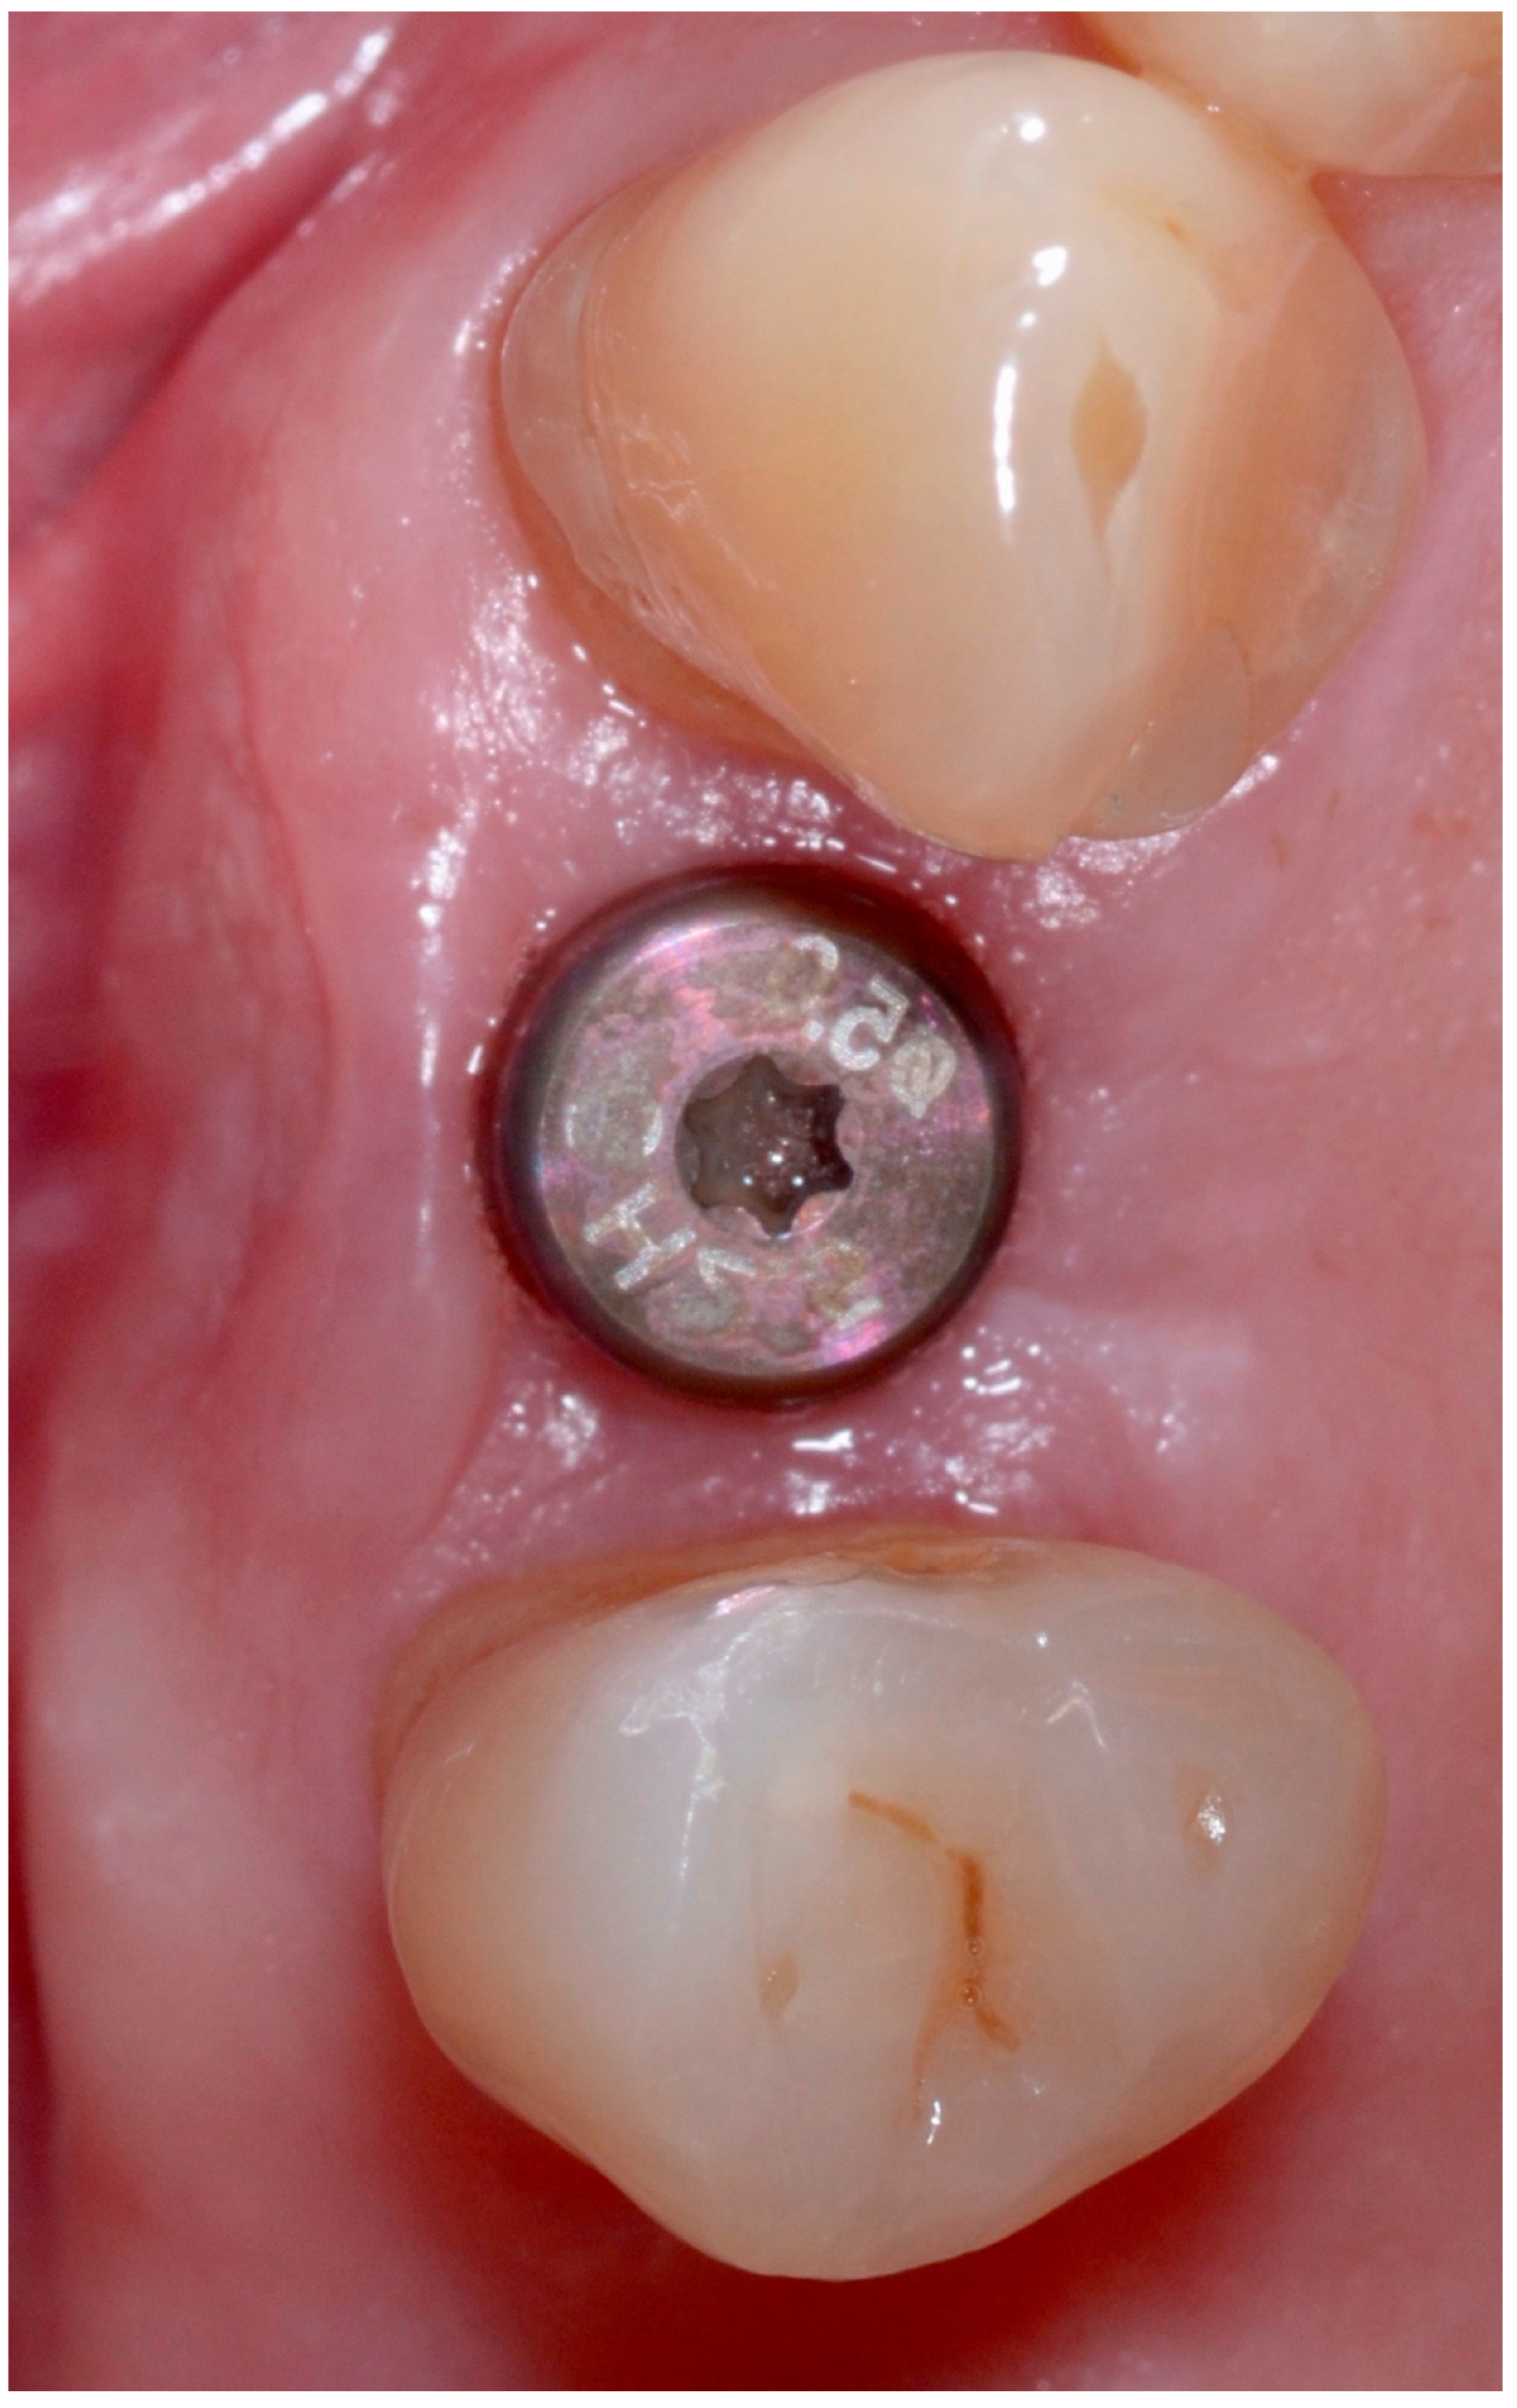

5.5. Implant Placement

5.3.1. Implant Stability

5.3.2. Marginal Bone Loss